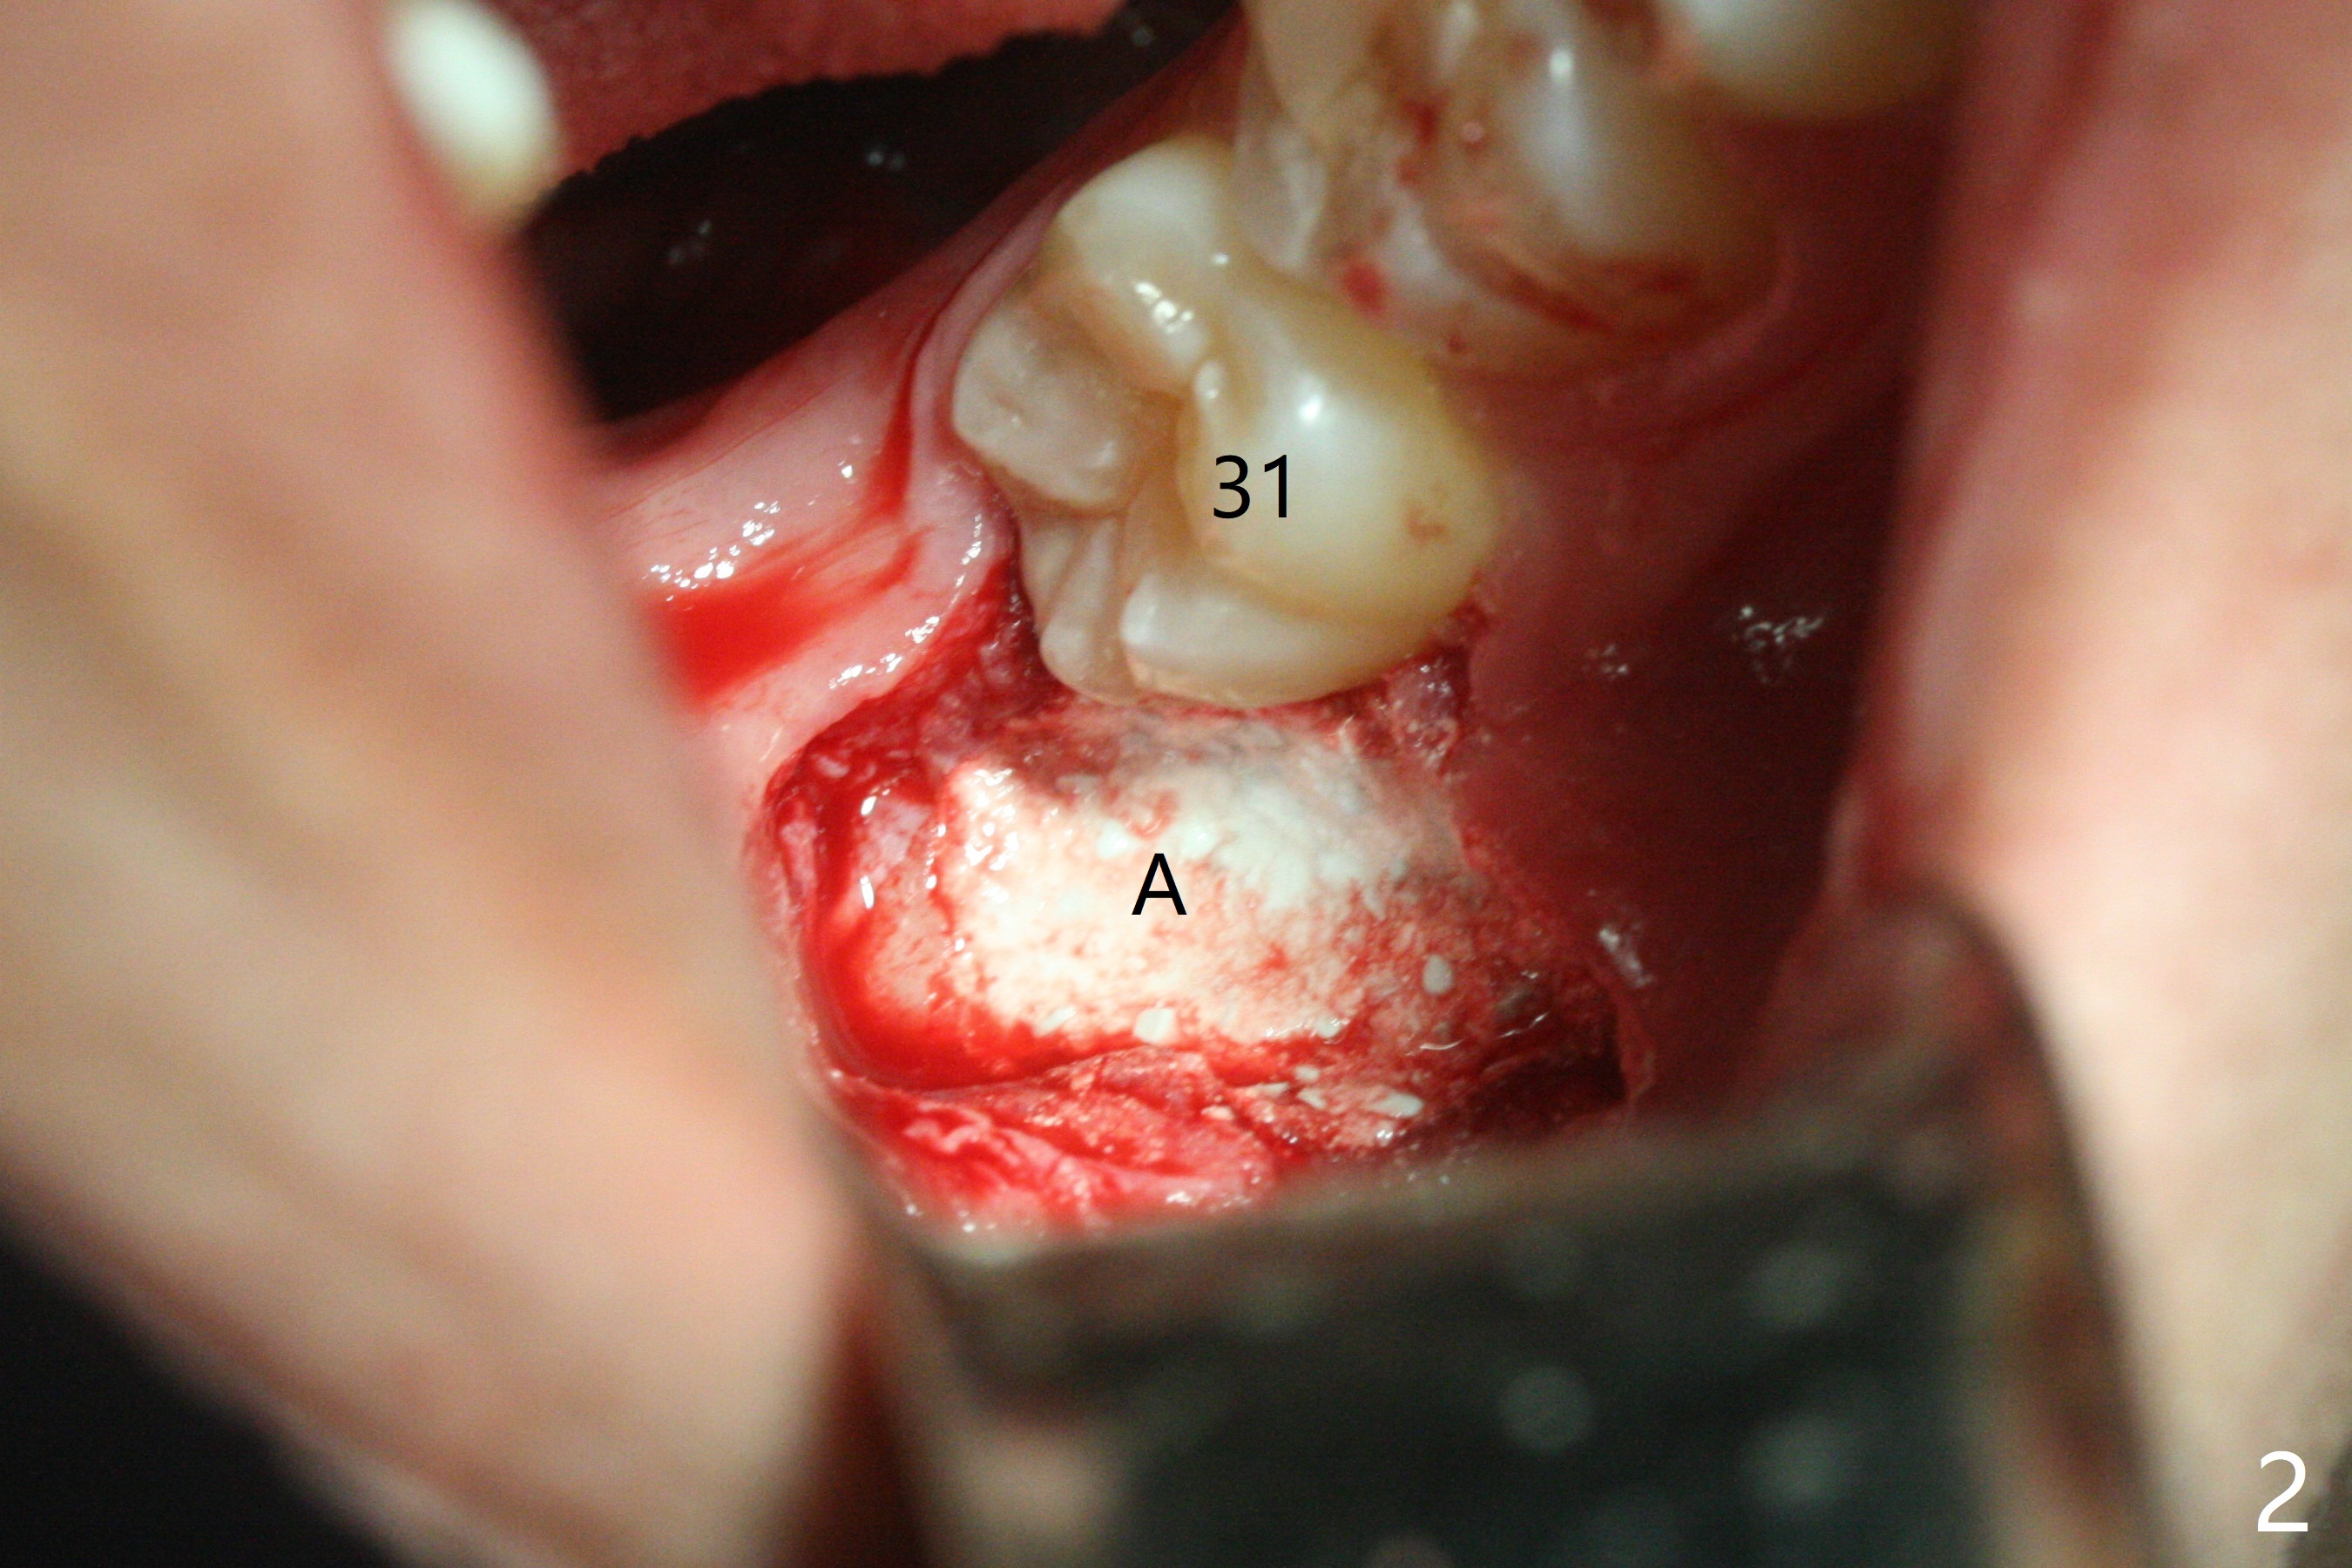

A 22-year-old man, asymptomatic, is going to have #1,16,17 and 32 extracted (Fig.1, fully bony impaction).  For the large lower sockets (actually Buccal Impaction), collagen plug (Fig.3 C) is placed in the inferior half, while Bone Cement (Bond Apatite from Augma (Fig.2,3 A)) and Osteogen plug (Fig.3 O) in the superior half at #32 and 17, respectively.  4-0 Chromic gut suture is used to close the wounds.  The four sockets heal (with increased bone density) 4 months postop (Fig.4).